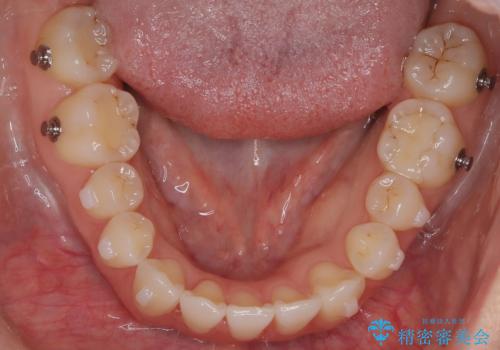

- 八重歯と、右上前歯(2番)が下の歯より内側に入っている反対咬合を気にされてご来院されました。精密な検査の結果、八重歯と反対咬合を同時に改善するためには、歯列全体にスペースを確保する必要があると判明。患者様のご希望から、透明で目立たないインビザライン(マウスピース矯正)による治療計画を立案しました。奥歯全体を奥へ動かす遠心移動でスペースを作り、これらの複雑な問題を一括で解消することを目指します。

今回の矯正治療では、透明なマウスピース型の装置インビザラインを使用しました。治療は、緻密なデジタル計画に基づき、奥歯から順に歯列全体を後方へ移動させる遠心移動を実施。これにより、八重歯を正しい位置に並べるためのスペースを確保しました。同時に、右上の2番を前方に誘導することで反対咬合を解消。結果として、抜歯することなく八重歯と反対咬合という複数の問題が改善され、機能的で美しい歯並びを獲得していただけました。